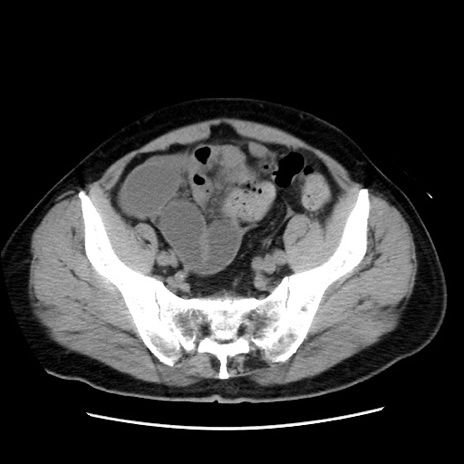

症例16(横断像)

【症例】 70歳代男性

【主訴】 腹痛、嘔吐

【現病歴】 約1ヶ月前より間欠的に腹痛と嘔吐あり、当院消化器内科を受診したところCTで多発する肝臓のLDAを指摘され、精査中であった。以降は消化器症状は安定していたが、2日前より嘔気と腹痛があり、同日より排便・排ガスが消失した。改善認めず、 本日、救急外来を受診した。

【既往歴】 大腸ポリープ切除後。

【身体所見】意識清明・会話良好、BT 36.3℃、BP 127/80mmHg、 P 80bpm、腹部:膨満あり、平坦・軟、上腹部正中および下腹部正中に圧痛あり、反跳痛なし、筋性防御なし。

【データ】WBC 7200、CRP 0.77